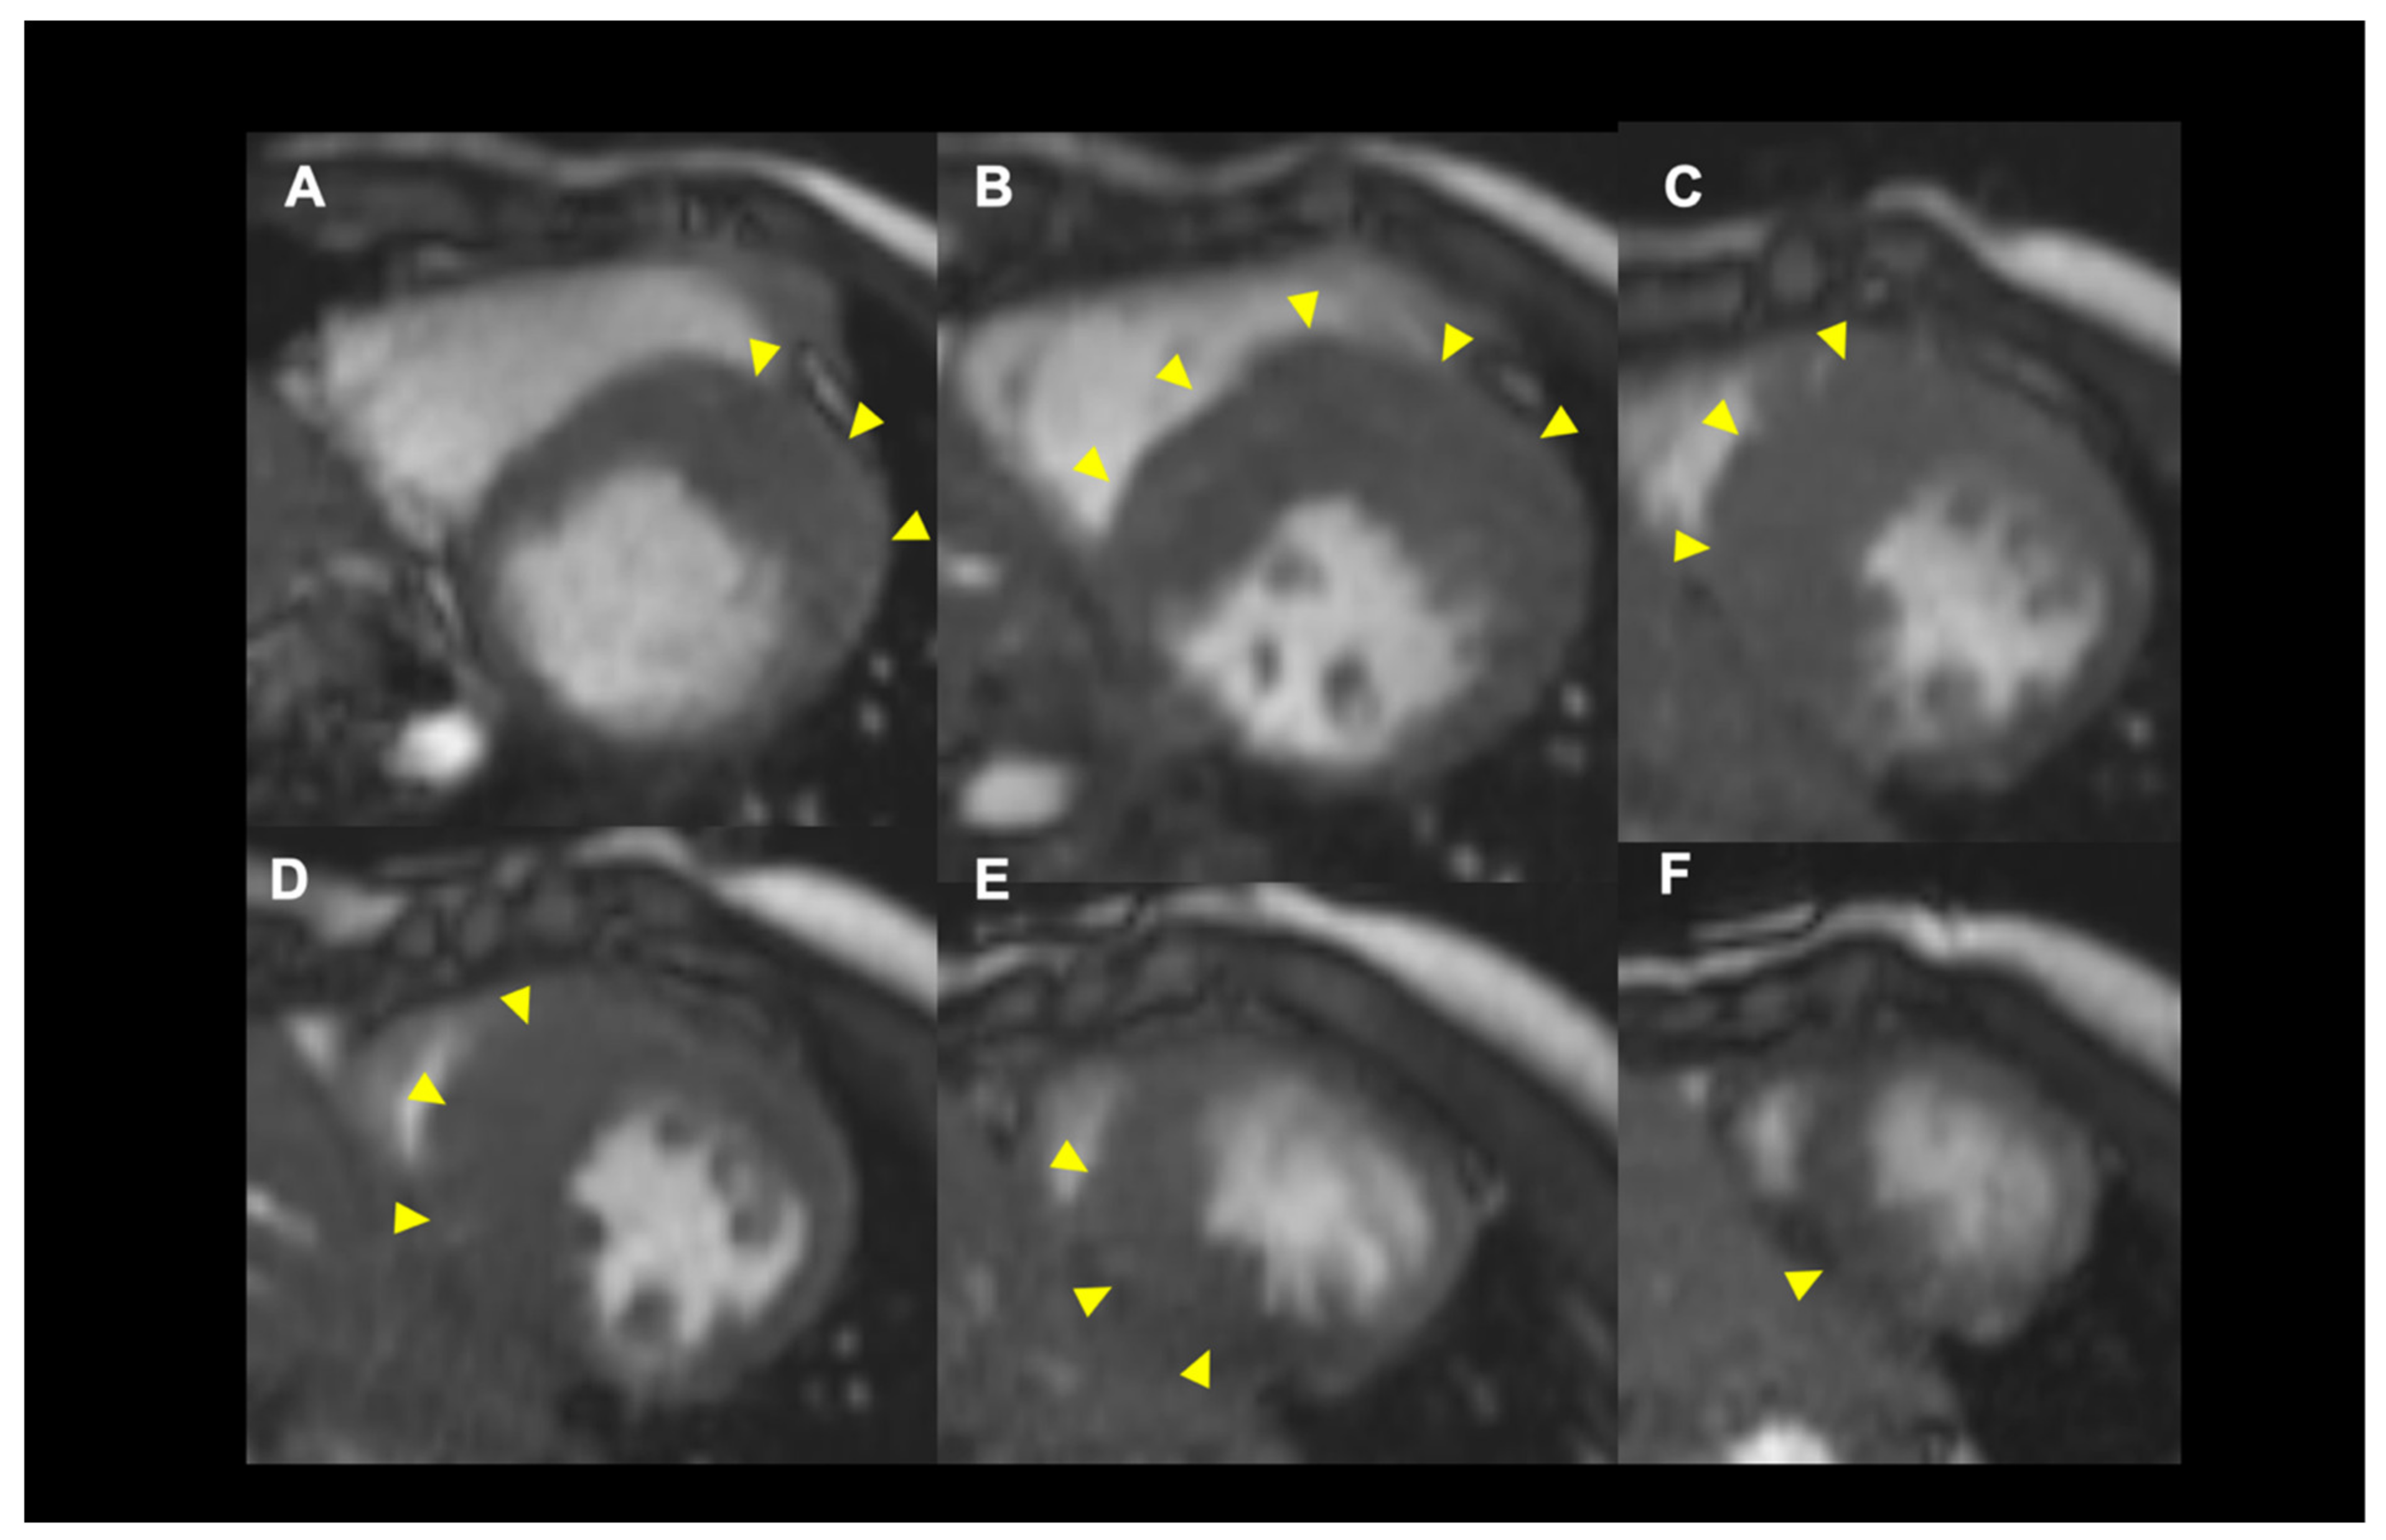

4.2. Role of Cardiac MRI for SCD Risk Stratification